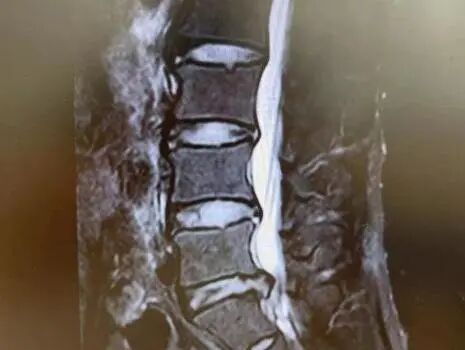

冀先生,73岁,腰疼5年伴双下肢无力2月余,行走200米后症状加重,间歇性跛行。入院完善检查诊断为:腰4-5椎间盘突出伴椎管狭窄。在全麻下行腰4—5椎管狭窄单侧入路双侧减压(UBE-ULBD)术后间歇性跛行缓解,下肢无力症状好转。

图片

病例二:

刘女士,73岁,左下肢疼痛伴间歇性跛行半年。经系统保守治疗后无缓解,入院完善检查诊断为:腰3-4椎间盘突出伴椎管狭窄。在全麻下行腰3-4椎管狭窄单侧入路双侧减压(UBE-ULBD)术后下肢疼痛缓解,无力症状缓解。